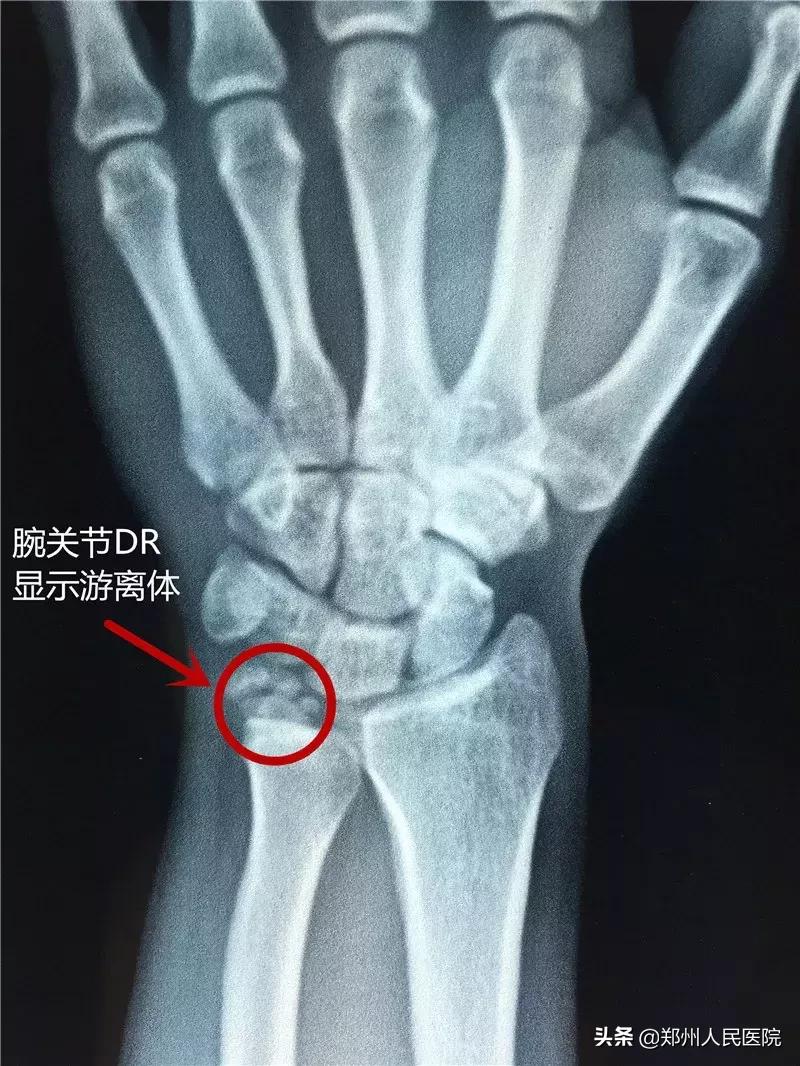

通过核磁、CT、平片等检查,骨三科副主任尹万乐发现患者右腕部三角纤维软骨盘撕裂并伴有撕脱骨折引起的游离体,想要彻底解决手腕疼痛的问题,需要进行关节镜下右腕关节探查术,对右腕部进行修整、缝合和清理。

术中探查发现患者右腕部三角纤维软骨盘破裂,关节软骨损伤,予以修复;破裂口底部可见游离体三枚,刨刀清理周围包裹软组织,取出游离体,探查无误后,缝合破裂的三角纤维软骨盘,缝合伤口,手术共用2小时。